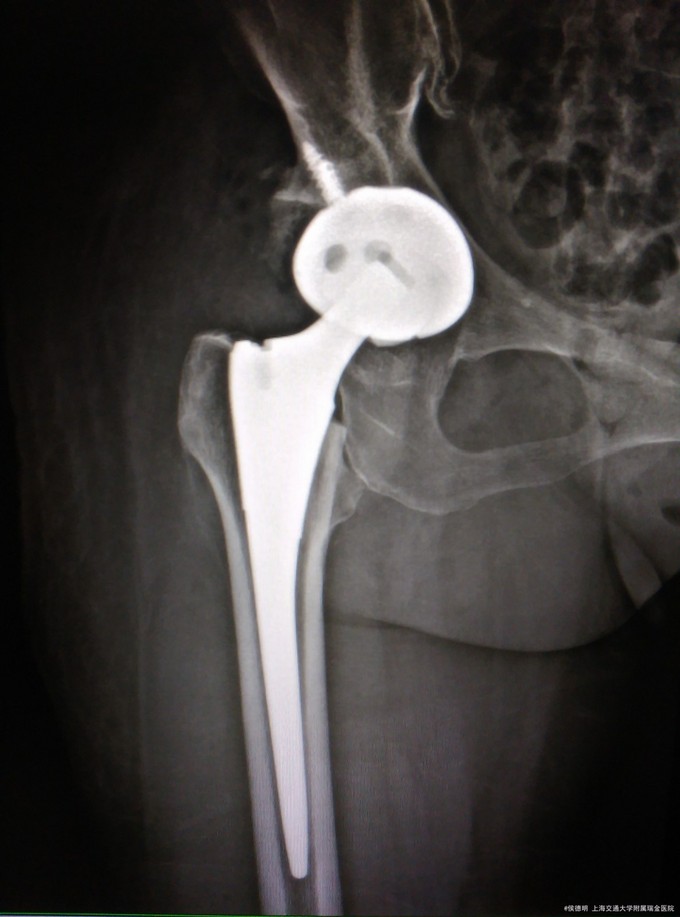

右侧髋关节发育不良,髋关节退变 右侧髋关节置换术

随访:术后2天拔出引流管。开始功能锻炼。 讨论:各位使用髋臼螺钉的指针是?对找到真正的髋臼底部有何经验?